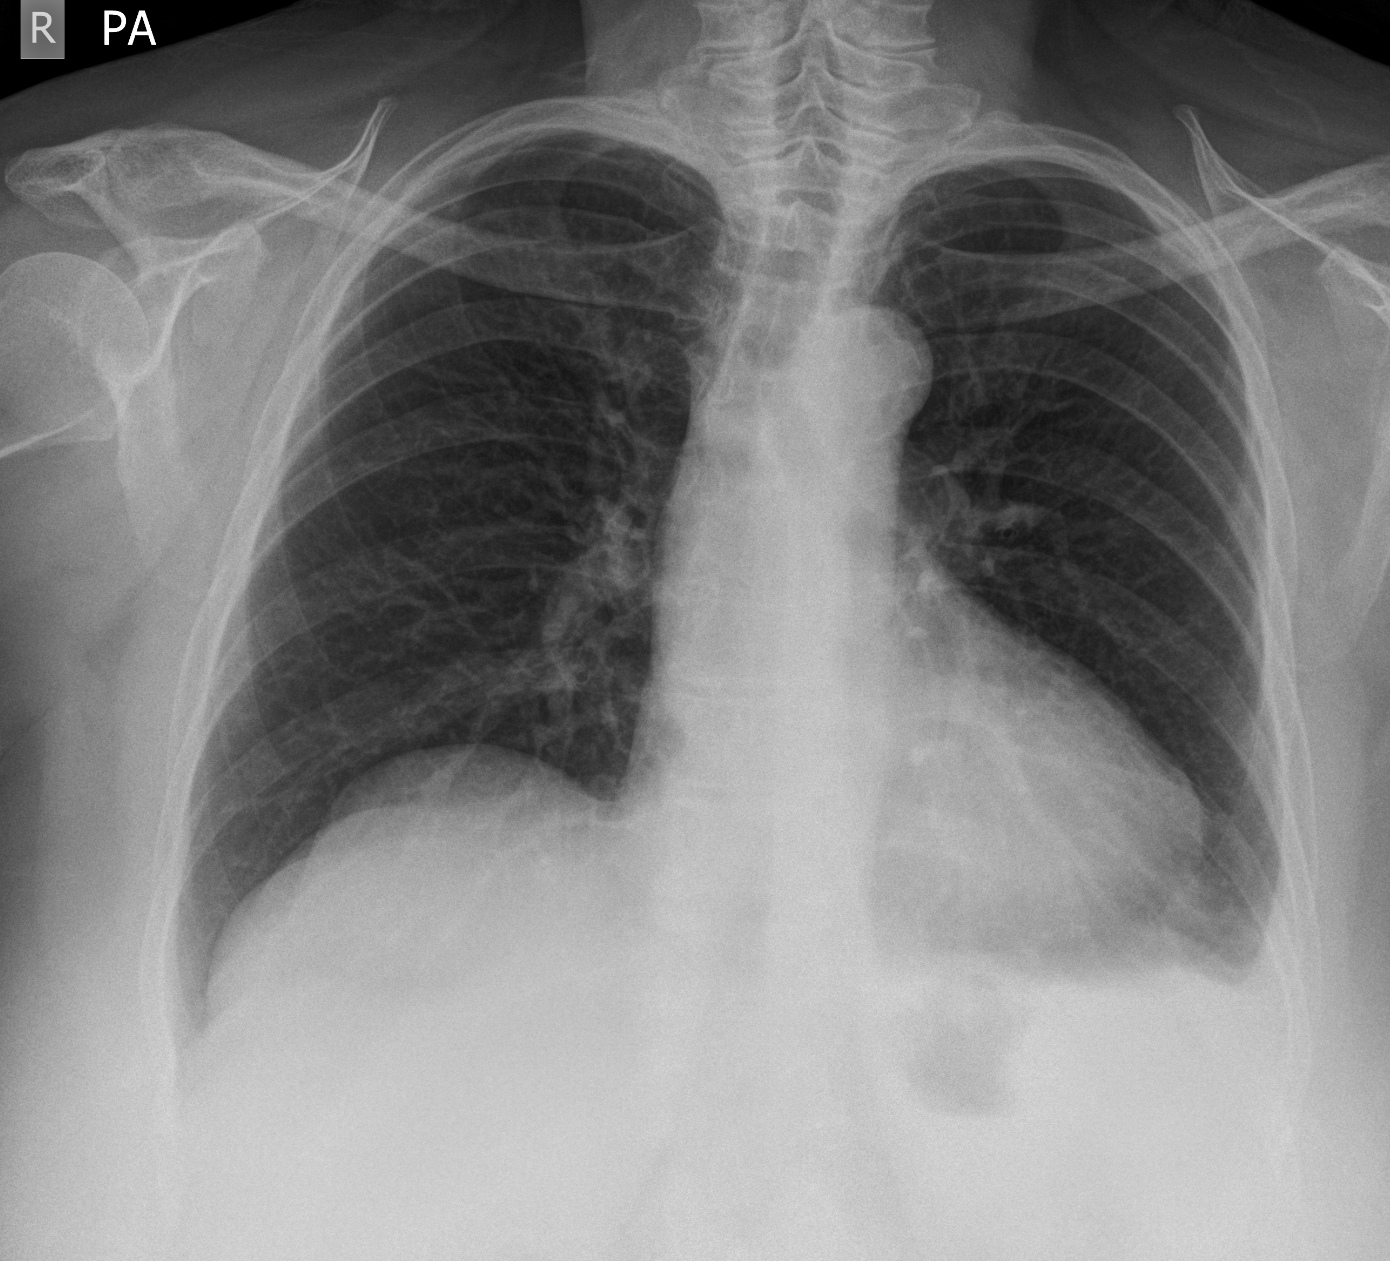

3. Pleural effusion and Pericardial effusion